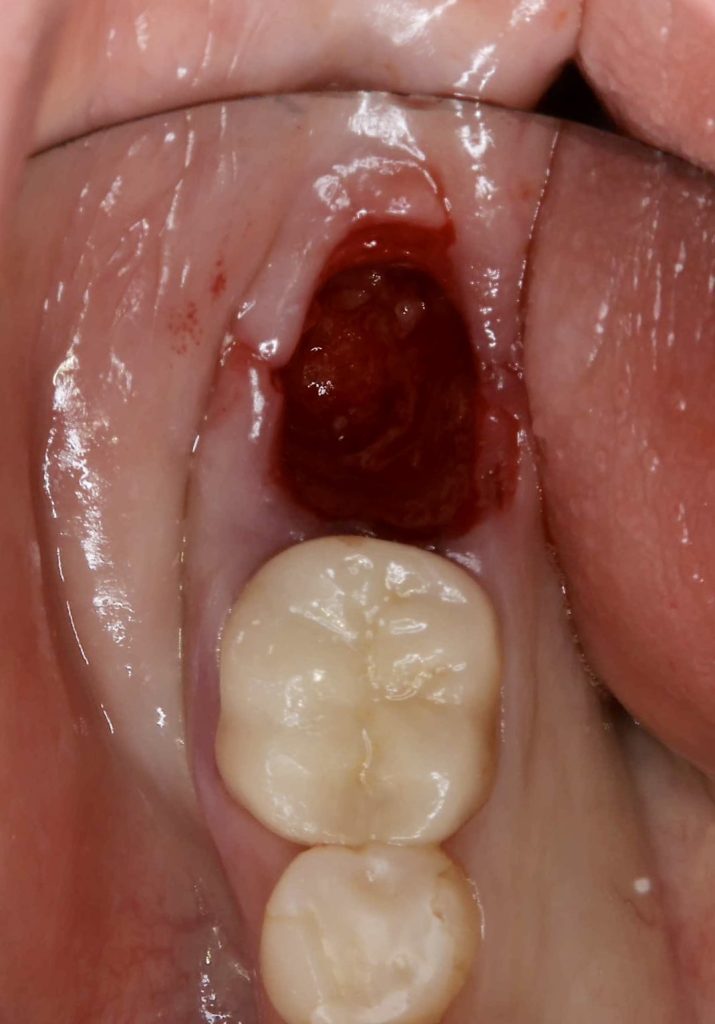

30代、女性、右下に違和感があることを健診中に申され、インプラント治療を行いました。

| 診断結果 | 右下7番歯根破折 |

| 治療内容 | 抜歯即時インプラント |